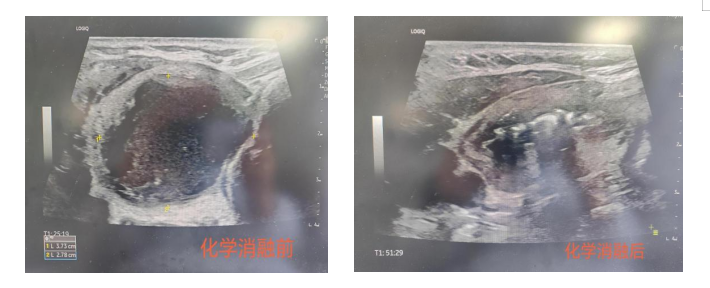

化學(xué)消融術(shù)案例:首例化學(xué)消融術(shù)患者為62歲男性,因頸部腫脹、吞咽伴異物感明顯就診,超聲檢查顯示其甲狀腺右葉存在直徑約4cm的囊性為主混合性腫物,已對氣管造成明顯壓迫。傳統(tǒng)手術(shù)需切除部分腺體,存在神經(jīng)損傷及終身服藥風(fēng)險。經(jīng)多學(xué)科討論,團(tuán)隊(duì)決定采用化學(xué)消融術(shù):在超聲引導(dǎo)下,將硬化劑精準(zhǔn)注入囊腔,通過化學(xué)作用使囊壁內(nèi)皮細(xì)胞失活,促進(jìn)囊液吸收。術(shù)后24小時,患者壓迫癥狀顯著緩解,復(fù)查顯示囊腔體積縮小60%以上。